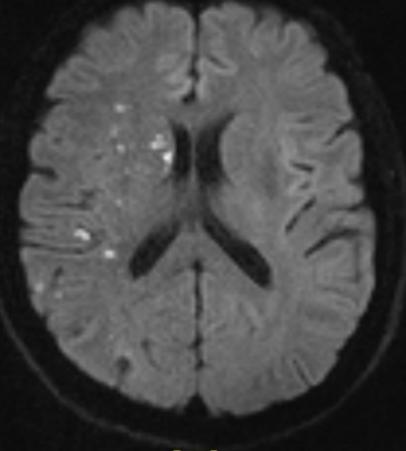

辅助检查:头颅MRI+MRA提示急性多发梗塞灶,右侧颈内动脉未见显影。

MRA示右侧颈内动脉未见显影

右侧大脑半球、基底节区多发梗塞灶

(急性期)